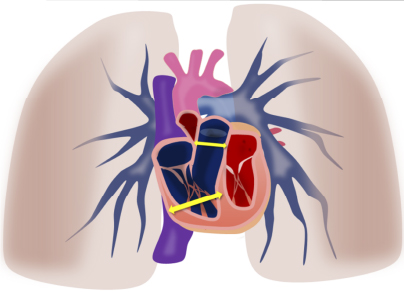

肺高血圧の特徴的な所見は

肺高血圧の特徴的な所見は右心負荷や肺動脈拡張です